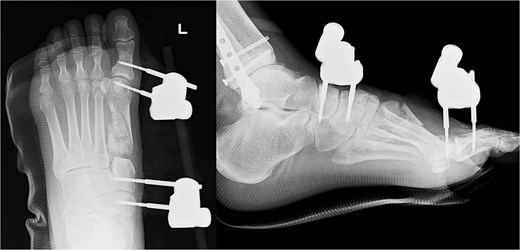

We performed surgery in two stages, owing to the poor condition of the skin. In the first stage, we performed screw fixation for the tibial pilon fracture and plate fixation for the distal fibular fracture. For the first-metatarsal fracture, half pins for external fixation were inserted into the first proximal phalanx, first metatarsal, medial cuneiform, and navicular bone. The external fixator (The Small External Fixation System, Synthes, Oberdorf, Switzerland) was stabilized with the first reduction in the metatarsal shortening deformity (Fig. 2). One week later, the second-stage surgery was performed after the swelling of soft tissues on the dorsum of the foot had improved. A longitudinal skin incision was made on the dorsum of the first metatarsal, and a fusion plate (Variable Angle LCP Forefoot/Midfoot system, Synthes) was placed on the dorsal aspect of the first metatarsal and the medial cuneiform. Three screws were inserted into the medial cuneiform, and four screws were inserted into the distal end of the first metatarsal. Postoperative radiography and CT images are shown in Fig. 3.